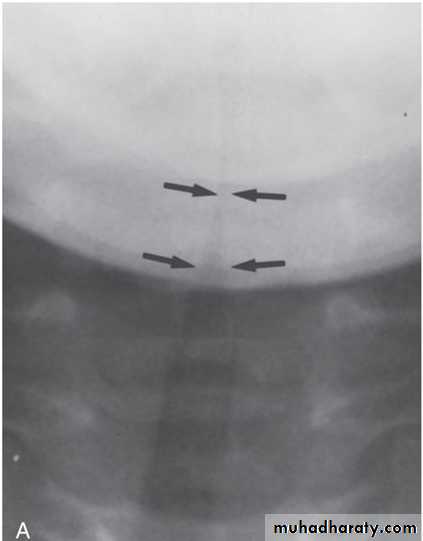

LABORATORY AND IMAGING STUDIESAnteroposterior radiographs of the neck show the diagnostic subglottic narrowing of croup known as the steeple sign.

PA view of the upper airway shows the so-called steeple sign, the tapered narrowing of the immediate subglottic airway (arrows)